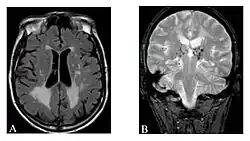

Magnetic resonance imaging (MRI) is a common form of biological data visualization used to form pictures of internal biological processes. Different settings of radiofrequency pulses and gradients result in different image appearances; these combinations are known as MRI sequences. A particularly notable subset of MRI is magnetic resonance angiography, which is a group of techniques used to image arteries and veins. MRI's imaging utility is further expanded upon by diffusion MRI and functional MRI, which can be used to capture neuronal tracts and blood flow respectively.

Diffusion MRI further relies on diffusion tensor imaging (DTI), which measures water molecule diffusion and directionality, and diffusion basis spectrum imaging (DBSI), which extracts multiple anisotropic and isotropic diffusion tensors.[39][40] Functional MRI relies on blood-oxygen-level dependent (BOLD) contrast, which measures the proportion of oxygenated hemoglobin in specific areas of the brain; this allows it to measure and model brain activity based on blood flow.[41] Further MRI techniques include saturation pulses (used to reduce motion artifacts), gradient echo (such as dynamic contrast enhancement), spin echo, and diffusion weighting (a signal contrast generation method based on differences in Brownian motion).[42][43][44]

In general, two aspects of the relaxation process are measured: the time taken for the magnetic vector to return to its resting state (also known as T1 or spin–lattice relaxation), and the time taken for the axial spin of the hydrogen protons to return to its resting state (also known as T2 or spin–spin relaxation).[47] To create a T1-weighted image, the MR signal is measured by changing the amount of time between RF pulses (also known as the time to repeat, or TR). To create a T2-weighted image, the MR signal is measured by changing the amount of time between delivering the RF pulse and receiving the RF energy signals from the hydrogen protons (also known as the time to echo, or TE). The dominant signal intensities of T1 image weighting are fluid (black due to low intensity), muscle (grey due to intermediate signal intensity), and fat (white due to high signal intensity). Fat suppression is applied to many T1 weighted sequences to suppress the brightness of the signal created by it. The dominant signal intensities of T2 image weighting are fluid (white), muscle (grey), and fat (white). T2 signals are also often emphasized or suppressed depending on what the goal of the imaging is; notable examples include fat suppression, fluid attenuation, and susceptibility weighting.